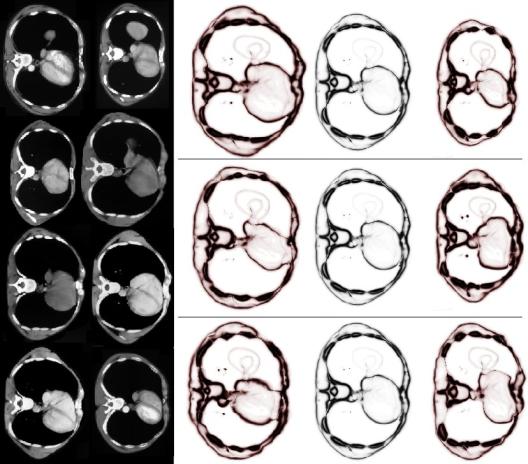

Angiogenesis, the formation of blood vessels and vessel networks, is a complex process governed by various biological mechanisms. If these mechanisms are disturbed, for instance in genetically modified organisms, the resulting vessel networks often exhibit abnormalities. In zebrafish embryos, for example, the hindbrain vasculature typically develops from two parallel veins (the primordial channels) by sprouting of several central arteries which then interconnect. In specific mutants, though, the resulting number of arterial-venous connections is strongly decreased.

To better understand the influence of the different involved biological parameters, the abnormality of the blood vessel system has to be quantified via mathematical tools. It is not obvious how to achieve such a quantification since even vessel systems of healthy individuals can vary strongly in their geometry and topology or connectivity. We will develop and test appropriate similarity measures between vessel systems and more general network structures based on mathematical models of optimal transport. Such a similarity measure can then be employed to define an average vessel system, to identify the strongest variation among a set of vessel systems, to distinguish between healthy and non-healthy individuals, and to analyse the temporal evolution of the vascular network.